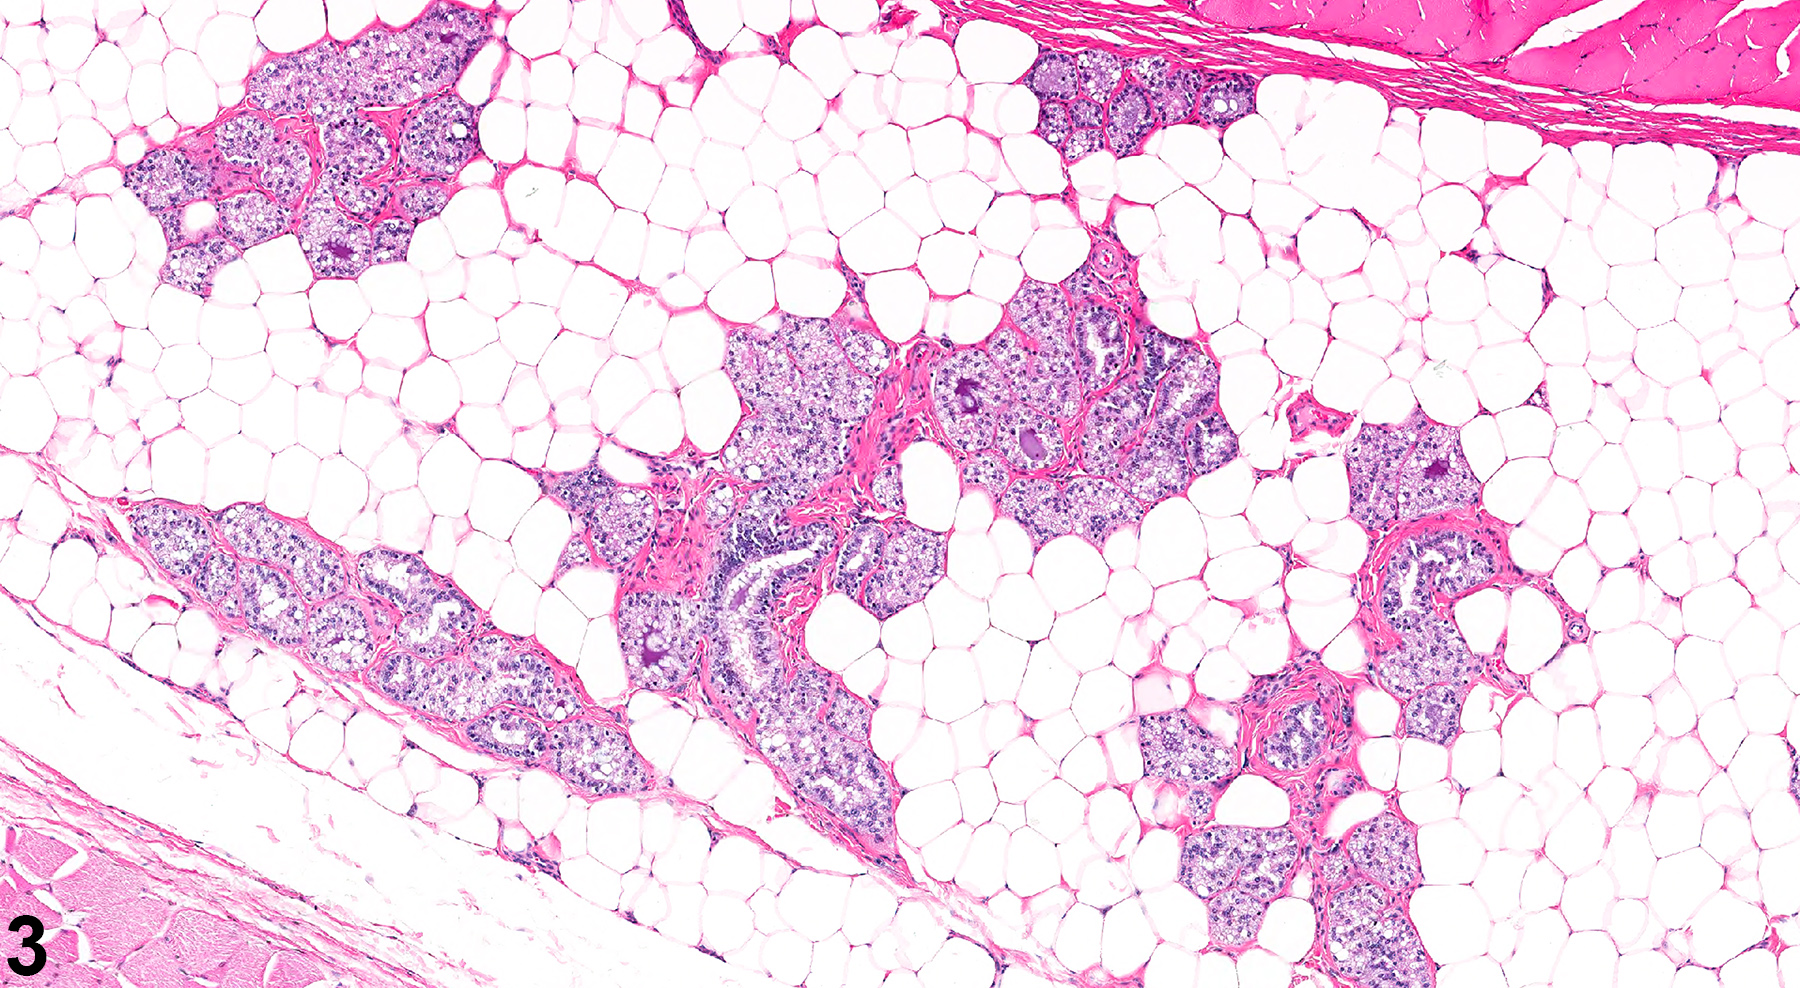

Male mice and rats normally have abundant mammary gland tissue, which can also undergo spontaneous or treatment-related hyperplasia. Unlike mice and other species, the mammary glands of rats exhibit sexual dimorphism, with glands in non-pregnant and non-lactating females having a tubuloalveolar morphology, while males exhibit a lobuloalveolar appearance. Thus, administration of certain agents (androgens, anabolic steroids, etc.) to female rats can result in the alteration of the mammary gland morphology to the typical male-like lobuloalveolar morphology (“masculinization” or “virilization”). Figure 3 and Figure 4 illustrate the mammary gland with a lobulolalveolar pattern (similar to that in control males) from a female rat dosed with oxymetholone (an anabolic steroid) for 13 weeks; the appearance is quite different from the usual female tubuloalveolar morphology observed in control female rats from the same study.